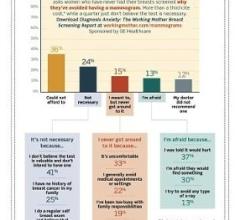

While most women understand the importance of health screenings, an estimated 72 million have missed or postponed a ...

A new survey entitled "Diagnosis Anxiety: The Working Mother Breast Screening Report" sheds important new information on the level of awareness women have about breast cancer today and what they are doing to help reduce the disease or detect it early.